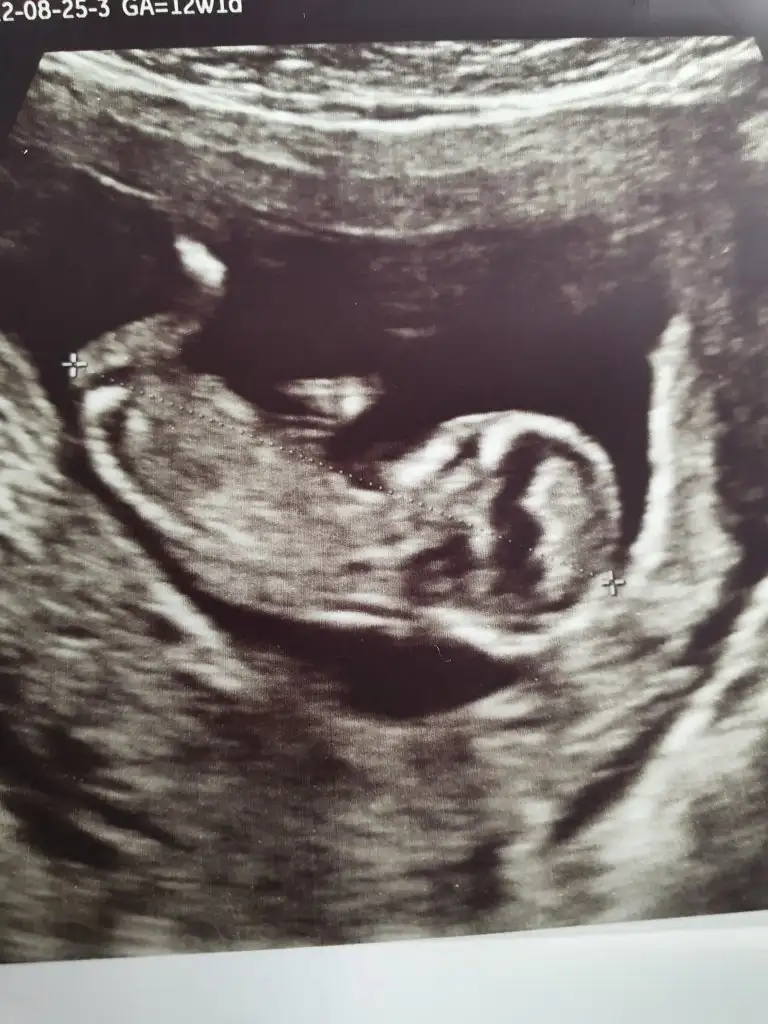

Banada bakarmısınız rica etsemHayırlı olsun

Merhaba banada tahmin yapar misinizKız bu